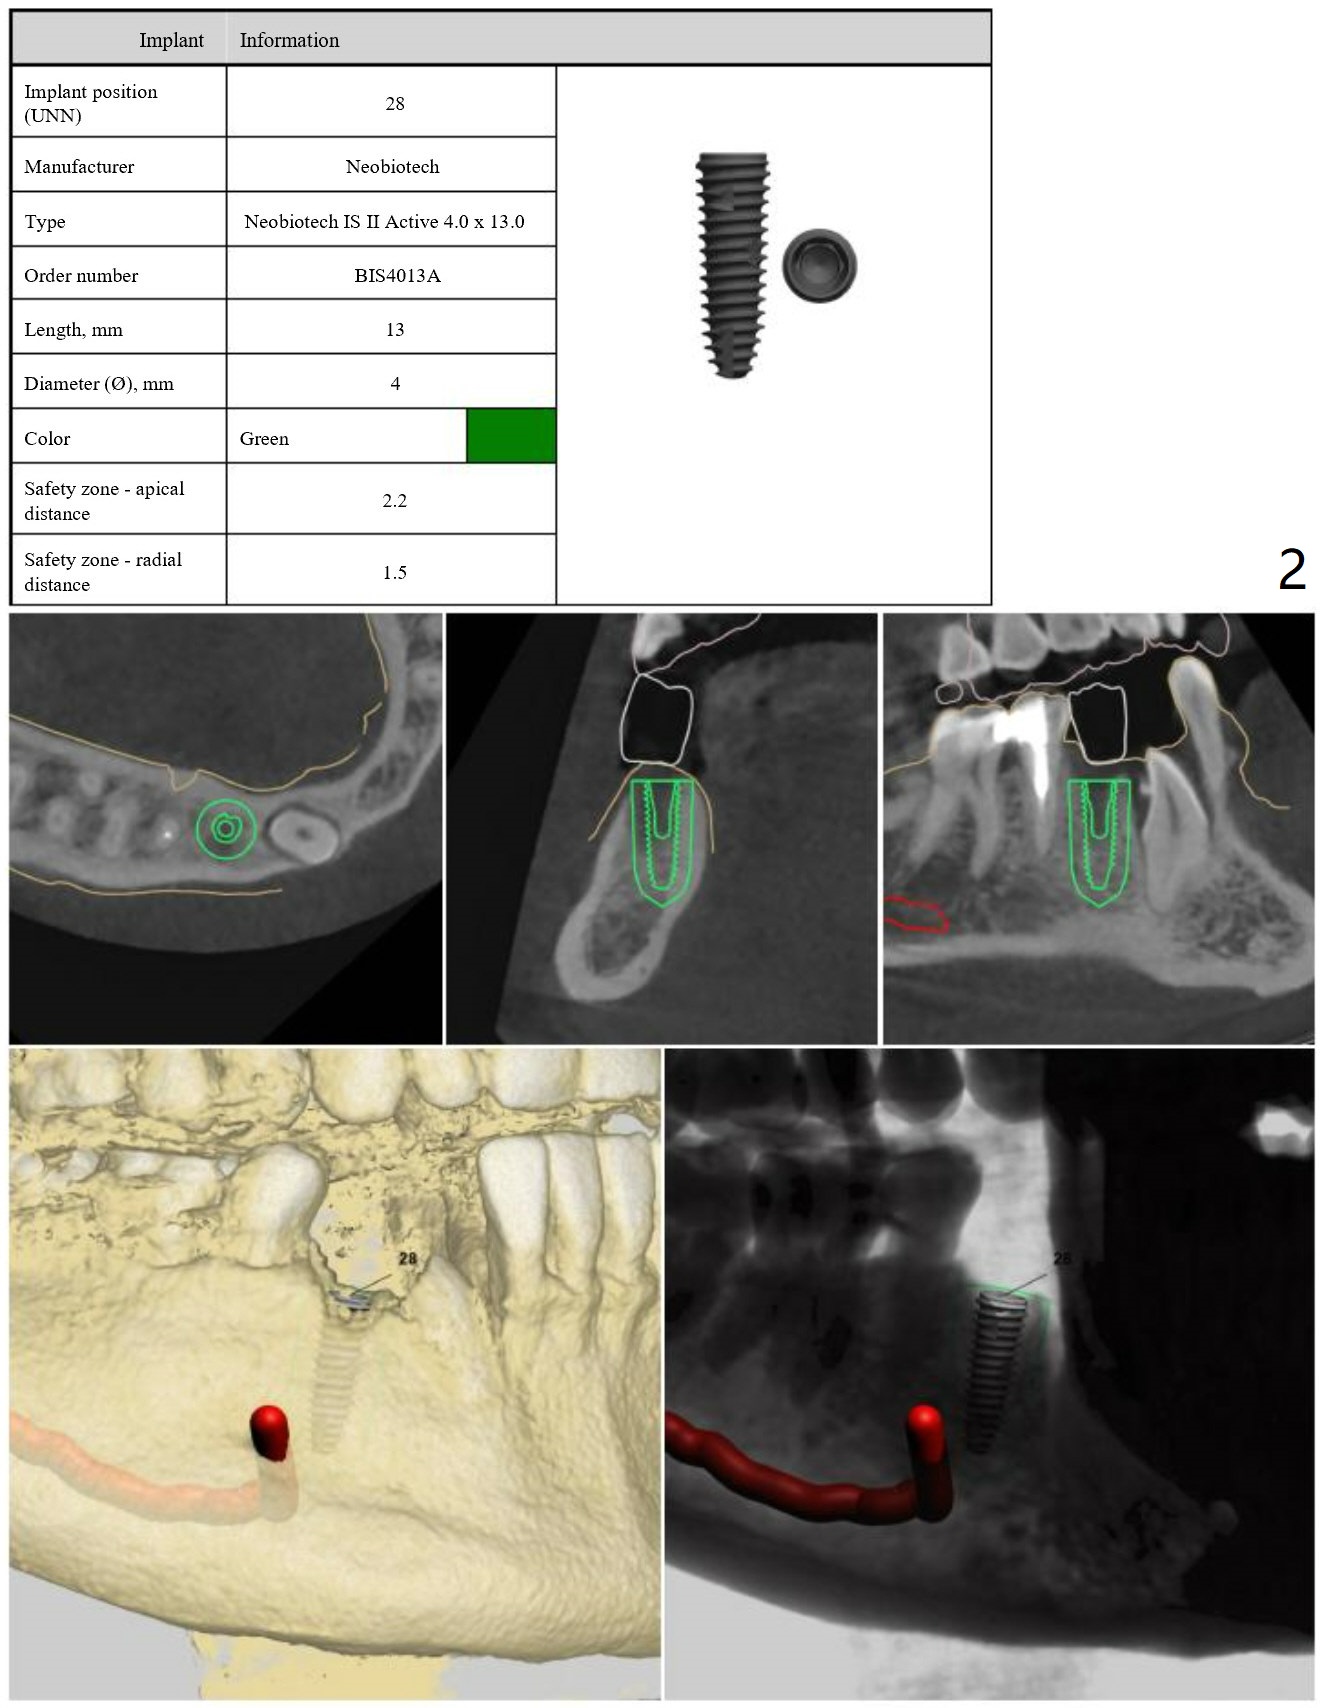

A 30-year-old man had the tooth #28 extracted with no bone graft. Allograft will be placed post implantation.

Lower Premolar

Immediate Implant,

Trajectory